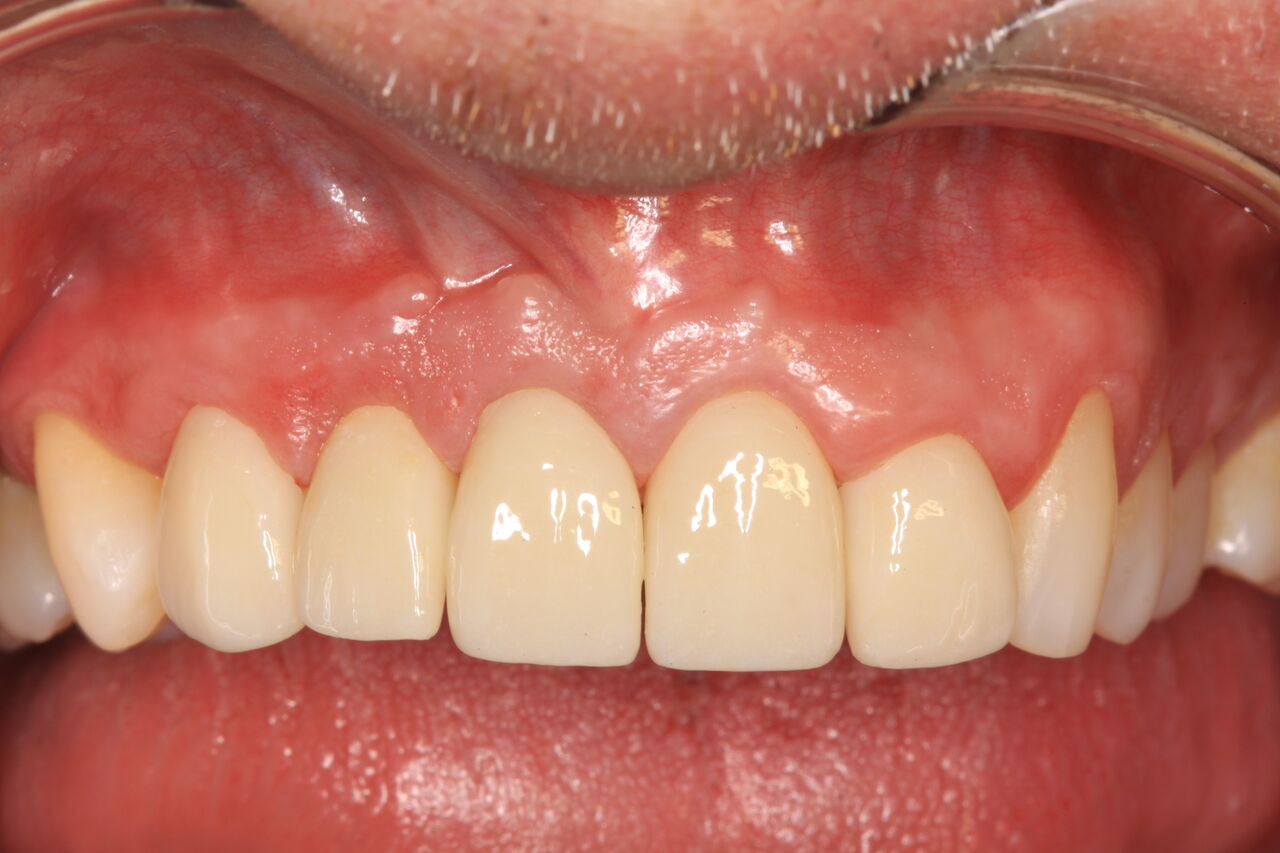

(22.) Temporary crowns on Nos. 6 through 10 at integration confirmation.

Figure 22

(23.) Soft tissue maturation at integration confirmation at 6 months.

Figure 23

A 42-year-old man presented with a very loose bridge on Nos. 6 through 9 with periodontally compromised retainers on Nos. 6 and 9 (Figure 17 through Figure 19), and endodontically involved No. 10 with a calcified canal. Teeth Nos. 6, 9, and 10 were extracted, the sockets fully debrided, and pontic soft tissue on Nos. 7 and 8 sculpted to be symmetrical in soft tissue contour with the contralateral lateral incisor and central incisor locations. Implants were secured in position Nos. 6 through 10 (Figure 20) in excess of 45 Ncm, the bone was milled to provide unimpeded seating of temporary abutments, and temporary crowns were fabricated chairside and adjusted to be out of occlusion in centric relation and all excursions. The temporary crowns were cemented after extrusion of excess cement extraorally and the patient was prescribed antibiotics, analgesics, and instructed in postoperative care particular to immediately provisionally restored implants. At 6 months, integration was confirmed (Figure 20 through Figure 23) and after placement of scanning abutments, the implants and soft tissues were scanned. Final crowns were fabricated from the scanned images and were cemented after extrusion of excess cement extraorally (Figure 24 through Figure 26), and oral hygiene procedures were reviewed.